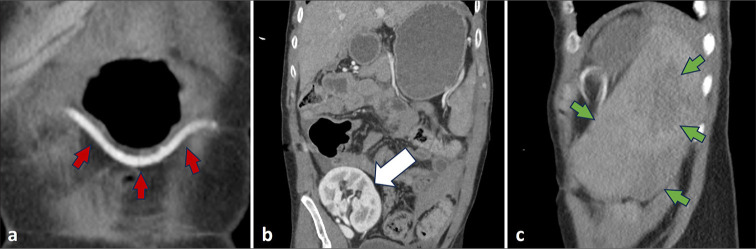

The spleen is a highly vascular organ susceptible to injury in blunt abdominal trauma, often leading to massive blood loss. Splenic artery embolization (SAE) has been shown to be a safe and effective nonoperative approach in cases of hemodynamically stable patients with blunt splenic trauma. SAE can be performed proximally or distally, with both approaches demonstrating similar clinical efficacy. This case report describes emergent splenic embolization for acute abdominal trauma in a liver transplant recipient. However, due to the presence of prior splenic artery ligation, a uniquely alternative route through the gastroepiploic artery was used to gain access to the spleen for embolization.

Abstract Image